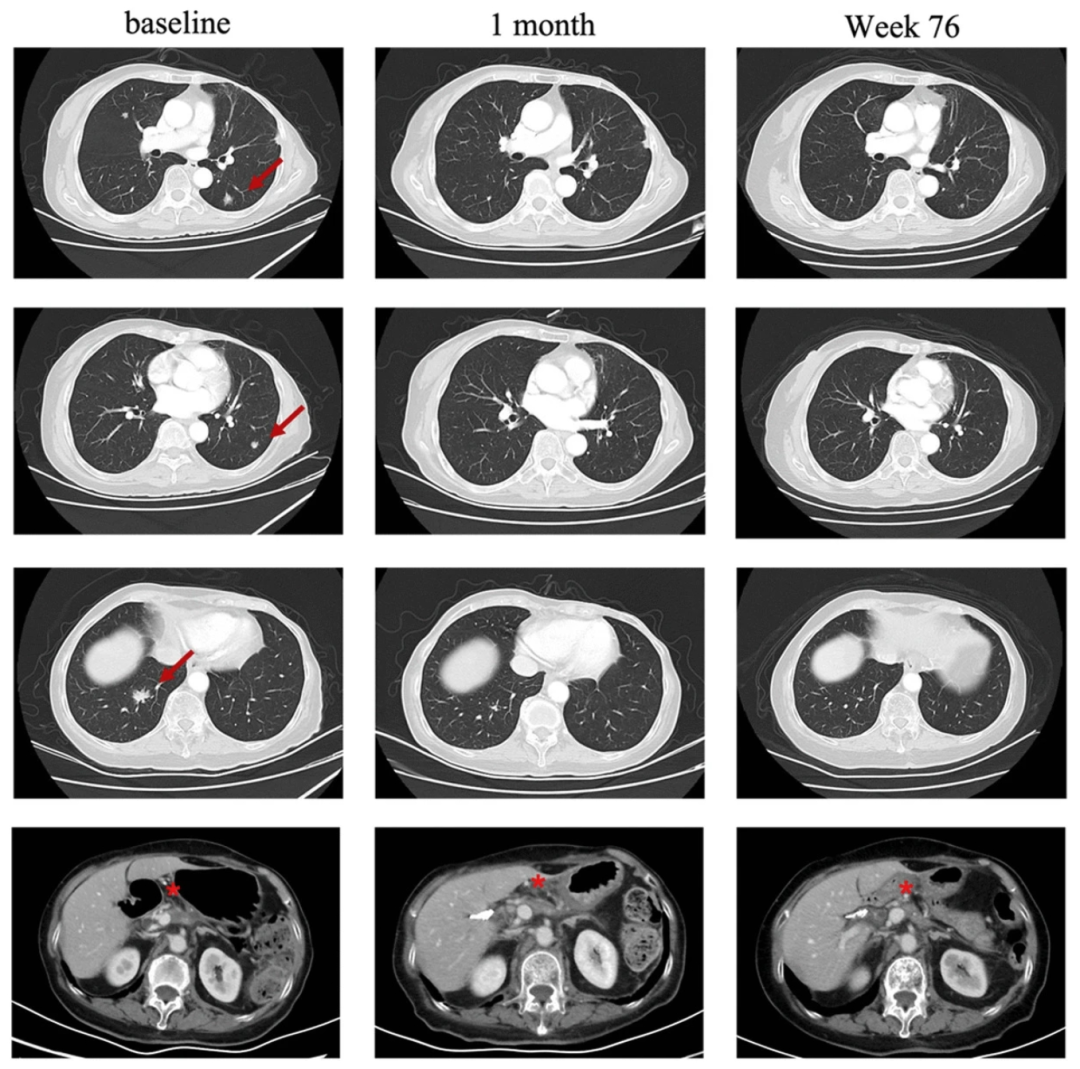

一项“CT041治疗胰腺癌”的临床研究,纳入一例75岁pT2N0的胰腺癌患者,该患者既往接受手术和S-1单药化疗效果不佳,出现了肺部肿瘤进展表现。因CLDN18.2表达确定为3+/60%,该患者入组CT041临床试验。CT041是用于治疗Claudin18.2(CLDN18.2)阳性实体瘤的自体CAR-T细胞候选产品。

结果显示,该患者在CT041治疗第4周,达到部分缓解(PR);肺转移靶病灶随后消失,并达到完全缓解(CR)。截至2023年7月最后一次随访时,肿瘤仍控制良好。

图1 患者在CT041治疗前后,肺部病变的放射学评估

注:“红色箭头”表示“目标病变”。“★”表示“原发病变”